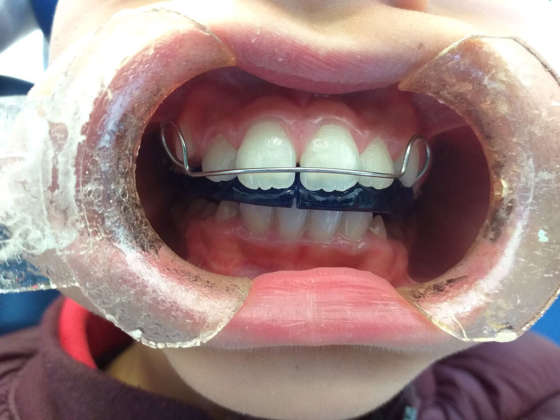

Tecniche di rilassamento psicologico e muscolare sono risultate efficaci nel ridurre i segni di bruxismo nei bambini di età inferiore ai sei anni (31), ma sfortunatamente l’educazione all’autoconsapevolezza e il biofeedback per controllare il bruxismo possono essere una sfida nei bambini. Allo stesso modo, sebbene ampiamente utilizzati per il trattamento del bruxismo negli adulti, i dispositivi orali (OA) non si sono dimostrati parimenti efficaci nei bambini (42) (Figure 1a-d). Probabilmente la causa risiede nelle preoccupazioni relative alla restrizione che si indurrebbe sulla crescita mascellare.

Nonostante ciò, nei bambini con segni e sintomi gravi di TMD, è stato recentemente suggerito l’uso di un OA con una vite di espansione centrale per consentire di seguire il normale sviluppo dei mascellari (43) (Figure 2a-c). Come sottolineato da Castroflorio T et al (19), le abitudini del sonno possono avere un ruolo rilevante nella patogenesi del bruxismo pediatrico, quindi le misure di igiene del sonno non dovrebbero essere a loro volta trascurate. Inoltre, in caso di diagnosi o sospetto di SDB, dovrebbe essere consigliato un trattamento appropriato.